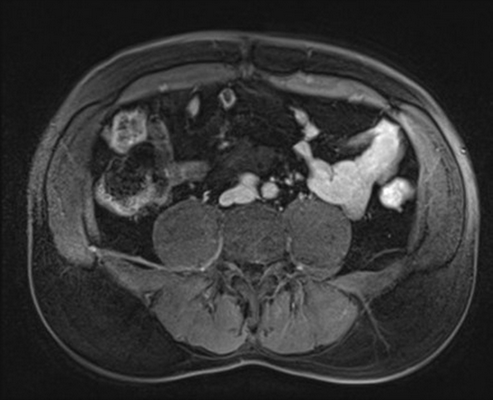

МРТ забрюшинного пространства, что показывает?

Магнитно-резонансная томограмма забрюшинного пространства

МРТ - неинвазивная высокоинформативная диагностическая процедура, позволяющая получить изображения с детальной трехмерной реконструкцией внутренних органов и структур человеческого тела. Исследование не подразумевает использования рентгеновских лучей и абсолютно безвредно для людей, не имеющих в организме металлических элементов. Физический принцип основан на регистрации энергии, выделяемой ионами водорода в молекулах воды под воздействием магнитного поля, и последующей компьютерной обработке данных. МРТ забрюшинного пространства не является диагностикой первой линии, проведение процедуры обосновано при малоинформативности прочих способов визуализации: УЗИ, экскреторной урографии, КТ, рентгенографии и др.

Для обеспечения максимальной контрастности патологического очага, изучения взаимоотношения последнего с соседними тканями, оценки сосудистого русла магнитно-резонансное исследование выполняют с усилением. Мера позволяет диагностировать злокачественные новообразования на доклинической стадии, когда выраженные симптомы отсутствуют. Преимущественно МРТ забрюшинного пространства назначают онкологическим пациентам и людям с противопоказаниями к использованию йодсодержащих препаратов.

В данной анатомической области с помощью магнитного сканирования можно выявить множество патологий. Что показывает МРТ забрюшинного пространства:

- Опухоли и кисты. Новообразования разделяют на исходящие из органов (почек, мочеточников, двенадцатиперстной кишки и др.) и свободных тканей (жировой клетчатки, мышц, фасций, нервных и лимфатических узлов, сосудов). Опухоли могут носить добро- или злокачественный характер, быть одиночными, множественными. Длительное время неопластический процесс протекает бессимптомно, жалобы появляются при компрессионном воздействии на близко расположенный орган. Объемное образование большого размера сдавливает сосудистые и лимфатические коллекторы, что приводит к застою крови в нижних конечностях, асциту (скоплению свободной жидкости в брюшной полости), расширению подкожных вен живота. Доброкачественная опухоль не вызывает раковой интоксикации, но может осложниться дисфункцией соседних органов. МРТ ретроперитонеального пространства показывает локализацию образования, позволяет предположить происхождение (в том числе - метастатическое), выполнить дифференциацию с абсцессом, гематомой, аневризмой брюшной части аорты. Окончательная диагностика невозможна без биопсии с последующим морфологическим исследованием. Из органных опухолей первое место занимают новообразования почек, второе - надпочечников.

- Травмы. Забрюшинная гематома формируется при прямом ударе в область поясницы или живота, дорожно-транспортном происшествии, падении с высоты. Часто сочетается с переломами костей и другими повреждениями. В экстренных ситуациях с выраженными клиническими проявлениями приоритетным исследованием остается компьютерная томография из-за быстроты получения результатов. КТ-сканы лучше в оценке кровотечений и переломов. МРТ может показать скрытые повреждения костей, связочного аппарата и пр.

- Изменения сосудов. При условии контрастирования на магнитно-резонансных томограммах видны аневризма, стеноз, атеросклеротические поражения, тромбообразование, аномалии развития и пр.

- Воспалительные процессы. Для неосложненных случаев достаточно УЗИ. Абсцессы и флегмоны рассматривают как осложнение воспаления органов с забрюшинной локализацией. С помощью магнитно-резонансного сканирования диагностируют параколит, паранефрит, перитонит, формирование свищевого хода. Исследование информативно для дифференциации хронического и острого панкреатита, пиелонефрита, гидронефротической трансформации, карбункула почки и пр.

МРТ ретроперитонеального пространства помогает установить причину патологических изменений, например, внешнее сдавление мочеточников опухолью и, как следствие, расширение чашечно-лоханочной системы. При выполнении контрастирования врач получает возможность судить о выделительной функции почек. Нефролитиаз и очаги кальцификации лучше оценивать при помощи КТ. Хроническое воспаление органов забрюшинного пространства может привести к развитию болезни Ормонда, характеризующейся избыточным продуцированием рубцовой ткани, что покажет магнитно-резонансная томография. Иногда фиброзный процесс является идиопатическим (без установления причины).